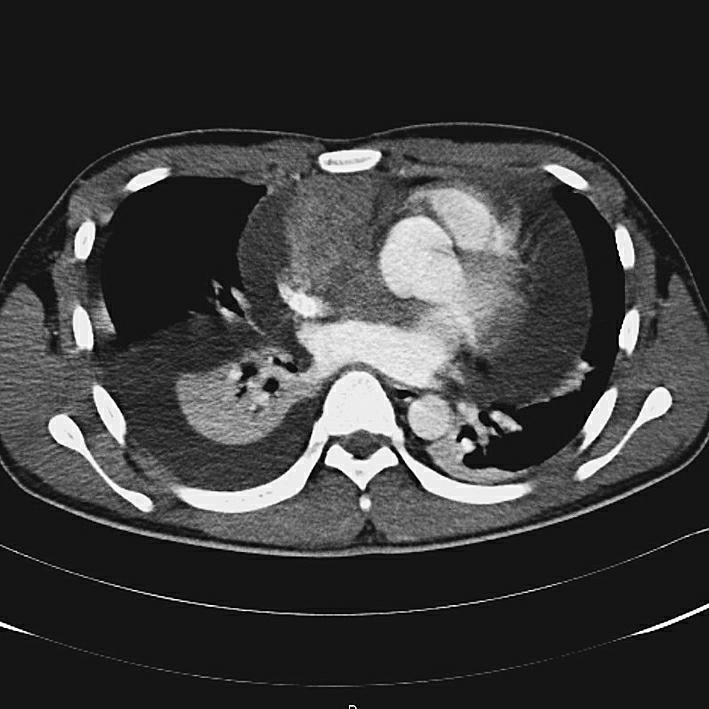

辅助检查:入院后行血常规、生化及结核与风湿免疫相关检验,均未见明显阳性结果,故考虑结核性心包积液可能性较小。后行心电图检查(2015年8月25日)示窦性心律,非特异性ST-T改变。X线胸片(2015年8月25日)示心影向双侧增大,呈烧瓶状。超声心动图(2015年9月1日)示舒张期心包腔内可见液性暗区:左室后壁21mm,右室前壁11mm,左室侧壁30mm,心尖20mm,右房顶10mm,剑突下20mm,心包腔内可见6.6cm×3.5cm实性团块,右室壁轻度受压(图1)。胸部增强CT(2015年8月26日)示心包腔内右心房上方见混杂密度肿块影,最大横截面积约6.1cm×4.0cm,病灶密度不均匀,伴有心包大量积液,少量右侧胸腔积液(图2)。心肌磁共振检查(2015年8月27日)示心包腔内团块状新生物,考虑恶性可能性大(图3)。随后在征得患者及其家属同意后,行PET-CT(2015年8月27日)检查,结果示心包腔内不均匀高代谢肿块,双侧颈根部及锁骨上窝多发高代谢肿大淋巴结,考虑恶性病变可能性大,伴随心包大量积液;右侧胸腔积液;腹、盆腔积液(图4)。综合以上检查及检验结果,考虑患者为恶性心包积液,心包腔内恶性病变可能性大,建议患者行穿刺活检,明确诊断。

图1心脏彩超

随访结果:患者于肿瘤科接受化疗,经2个周期(每7天1个周期)后,再次行超声心动图检查,结果是肿瘤体积缩小,为5.7cm×3.4cm,同时未见明显心包积液(图6)。

图6化疗后超声心动图